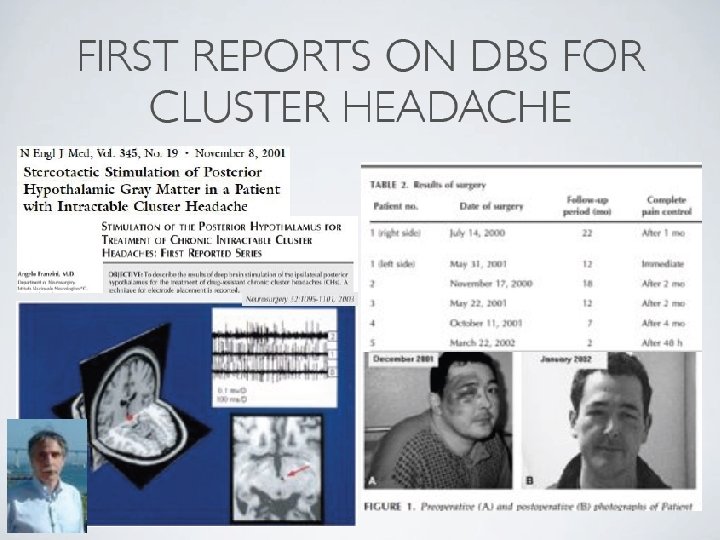

Neuromodulation for chronic intractable primary headache Laurence Watkins Victor Horsley Department of Neurosurgery National Hospital for Neurology & Neurosurgery BASH Hull January 2011